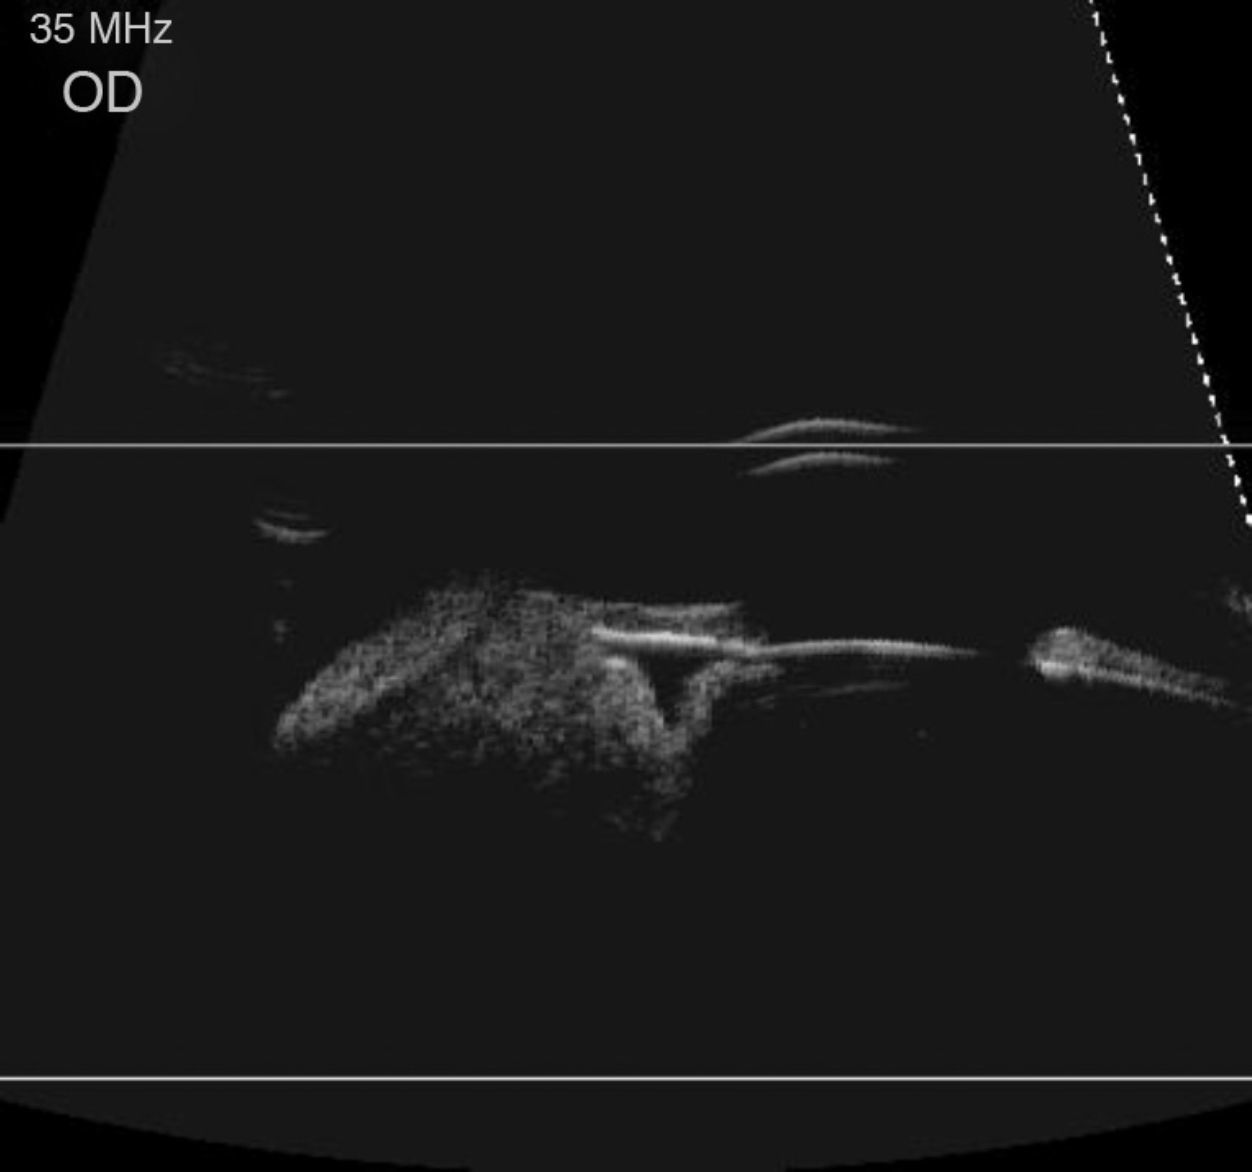

We report the cases of 2 women with a pigmented tumor in the ciliary body, one a melanocytoma and the other a melanoma, with different clinical manifestations. The first one presented with decreased visual acuity associated with recent growth of the tumor, as well as sectorial opacities of the lens and subluxation. The second one is asymptomatic and has been kept under observation for more than 30 years.

Se presentan dos casos de mujeres con una tumoración pigmentada en cuerpo ciliar, un melanoma y un melanocitoma, con diferentes manifestaciones clínicas. La primera refiere disminución de agudeza visual asociada a la tumoración de reciente aparición, así como subluxación y opacificación sectorial cristaliniana. La segunda está asintomática y ha permanecido en observación más de 30 años.